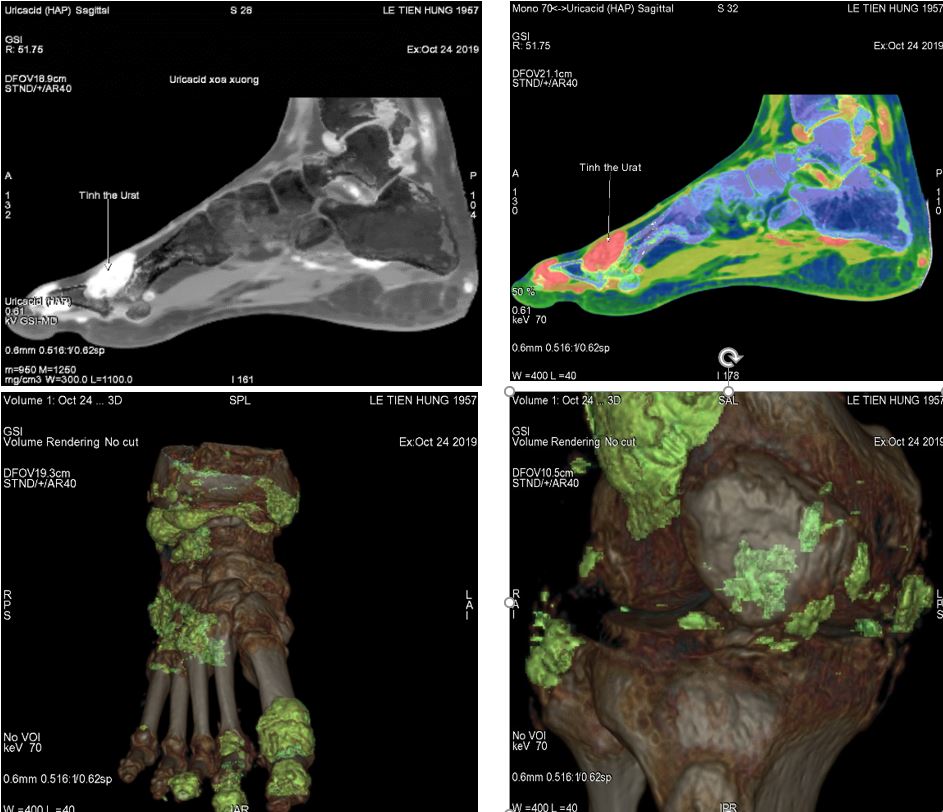

9. Lập bản đồ đánh giá của lắng đọng urat ở các khớp, mức độ phá hủy xương của các bệnh nhân bị Gout.

Hình ảnh GSI lập bản đồ đánh giá lắng đọng urat ở các khớp của bệnh nhân Gout